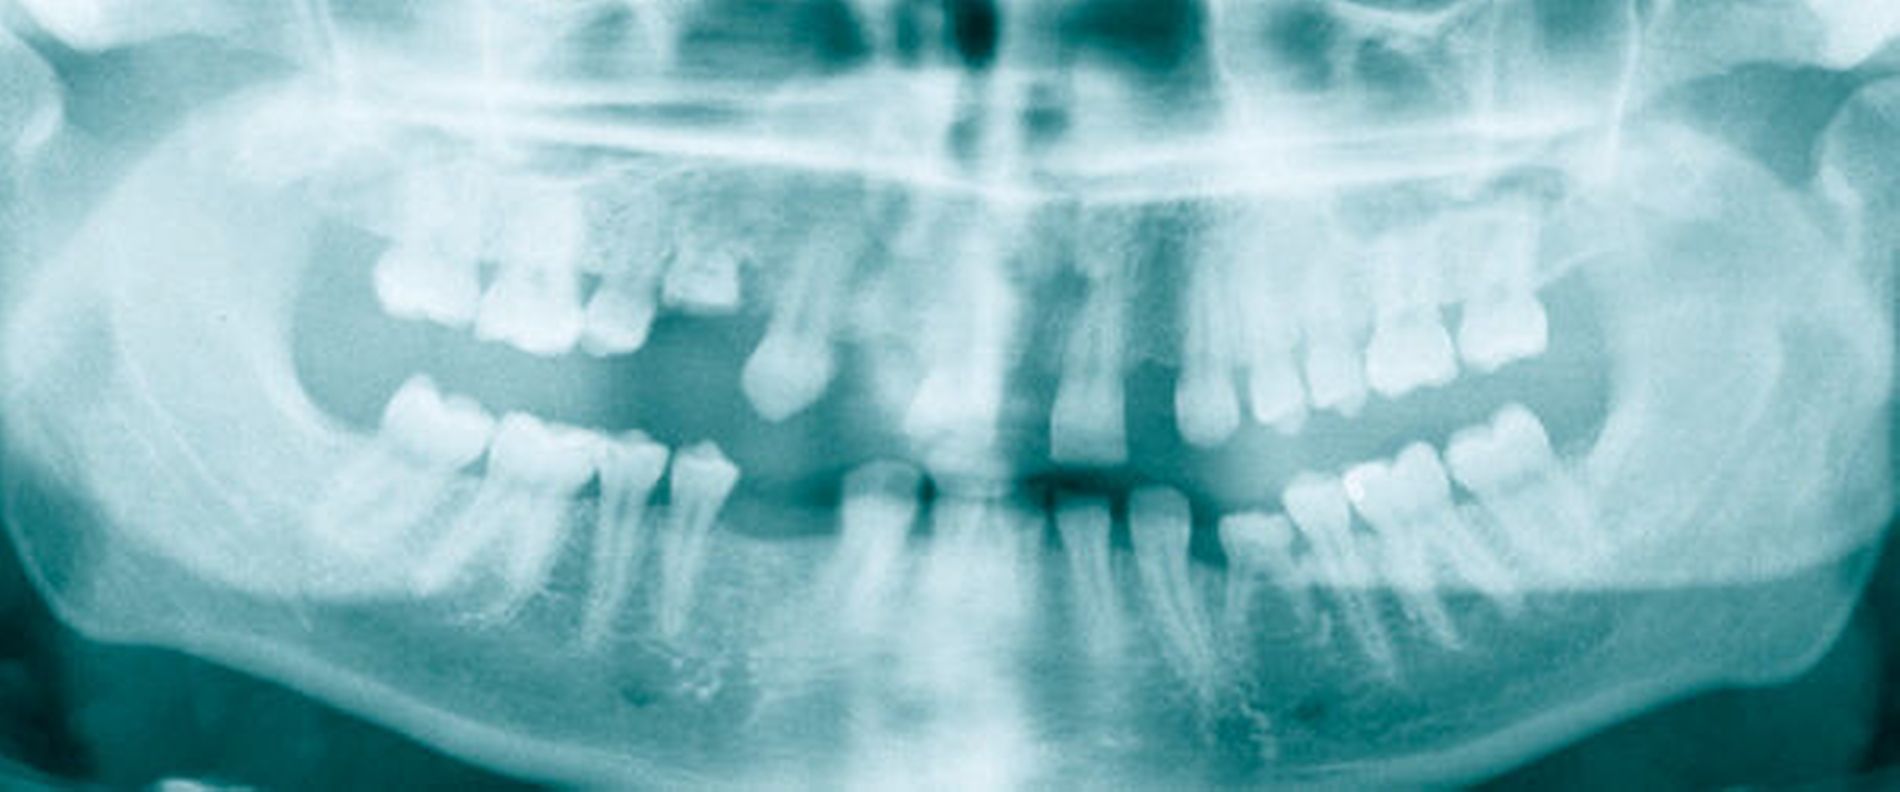

Anhand des klinischen Befunds, des Orthopantomogramms (Abbildung 3), der Durchzeichnung des seitlichen Fernröntgenbildes (Abbildung 4) und der Analyse der einartikulierten Modelle wurden folgende Diagnosen gestellt: skelettale und dentale Klasse II nach Angle (Distalbiss), Tiefbiss, Aplasie der Zähne 12, 14, 22, 34, 42, Persistenz und Infraposition der Zähne 54 und 74, Mikrodontie, starke Attrition der Oberkiefer- und der Unterkiefer-Front- und Eckzähne.

Unter Bisshebung auf Artikulator-montierten Modellen hergestellte Kunststoffprovisorien auf den Ober- und den Unterkiefer-Schneide- und -Eckzähnen und den Unterkiefer-Sechsern (Abbildung 5) wurden adhäsiv eingesetzt (Abbildung 6). Die so bewerkstelligte Vergrößerung der Zähne war Voraussetzung für die kieferorthopädische Behandlung.

Nach Abschluss der über circa drei Jahre plangemäß verlaufenen präoperativen festsitzenden kieferorthopädischen Behandlung wurde in Allgemeinnarkose der chirurgische Eingriff durchgeführt: Oberkiefer: eine Le-Fort-I-Osteotomie in zwei Teilen mit paramedianer Osteotomie zur Oberkieferverbreiterung, Kaudalverlagerung und Korrektur einer geringgradigen Mittellinienverschiebung (nach Vorgabe der therapeutisch einartikulierten Modelle) sowie Fixierung mit Miniplattenosteosynthesen Unterkiefer: eine bilaterale sagittale Spaltungsosteotomie mit Vor-Verlagerung, Bisshebung, Stellschrauben- und Miniplattenosteosynthesen. Die Überlagerung der postoperativen Durchzeichnung des seitlichen Fernröntgens mit der Ausgangssituation veranschaulicht die skelettalen Veränderungen (Abbildung 7).